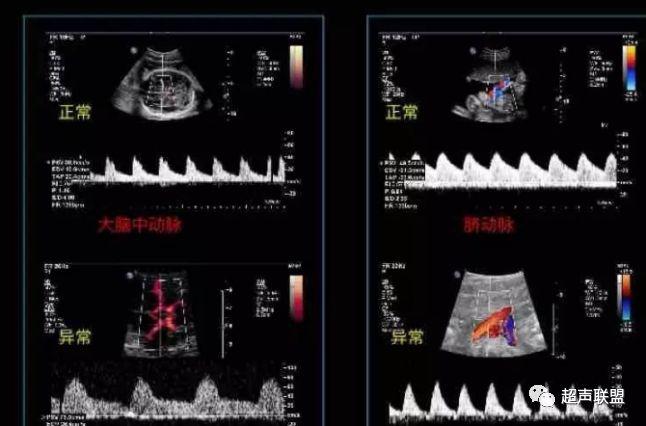

图3 正常大脑中动脉血流频谱

图4 大脑中动脉血流阻力减低

2 胎儿大脑中动脉测定

缺氧早期大脑血液供应增加,颅内血管扩张,阻力降低,舒张末期血流速度增加,PI、RI值下降,说明缺氧早期的血流再分配。当大脑中动脉RI、PI值明显下降,而脐动脉和腹主动脉的PI值升高,大脑中动脉PI值与脐动脉PI值的比值低于2个标准差时,提示严重缺氧的存在。

1、比值标准:大脑中动脉阻力降低,妊娠期,大脑中动脉RI <脐动脉RI;

4、当大脑中动脉RI及PI值明显下降,而脐动脉及腹主动脉的PI值之间升高,大脑中动脉PI值与脐动脉PI值低于两个标准差时,提示为胎儿严重缺氧;